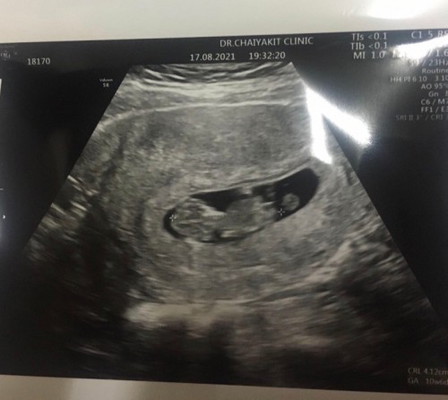

แม่ๆค่ะ วันนี้ไป U/S มา น้อง 10week 3 day หมอไม่ให้ฟังเสียงหัวใจเลย แต่เห็นน้องดิ้น ดุ๊กๆดิ๊กๆ ด้วย หมอ บอกไม่ต้องฟัง น้องโอเคดี มีแม่ๆ คนไหนเหมือนกันบ้างค่ะ

เหมือนกันคะ..แต่หมอซาวคะ .เพียงแต่ซาวดูเพศเลยช้า..แต่เราก็เห็นหัวใจลูกเต้นนะคะ..เห็นเพศหมอบอกแขนขายาวมากและรุ้ว่าน้องสมบูรณ์ก้ดีใจมากๆแล้วคะ

เราได้ยินเสียงหัวใจเด็กเต้นตั้งแต่ 7w ค่ะหมอซาวด์ผ่านช่องคลอดและหมอก็ให้ฟังเสียงหัวใจเด็กเต้นด้วยค่ะซาวด์ที่โรงบาลเอกชน

ครั้งแรก 7+1 วีค เห้นหัวใจ แต่หมอก้ไม่ให้ฟัง รอบ 2 13+1.วีค เห้นหัวใจเต้น แต่หมอก้ไม่ให้ฟังเหมือนเดิม จนต้องซื้อเครื่องมาฟังเองค่ะ